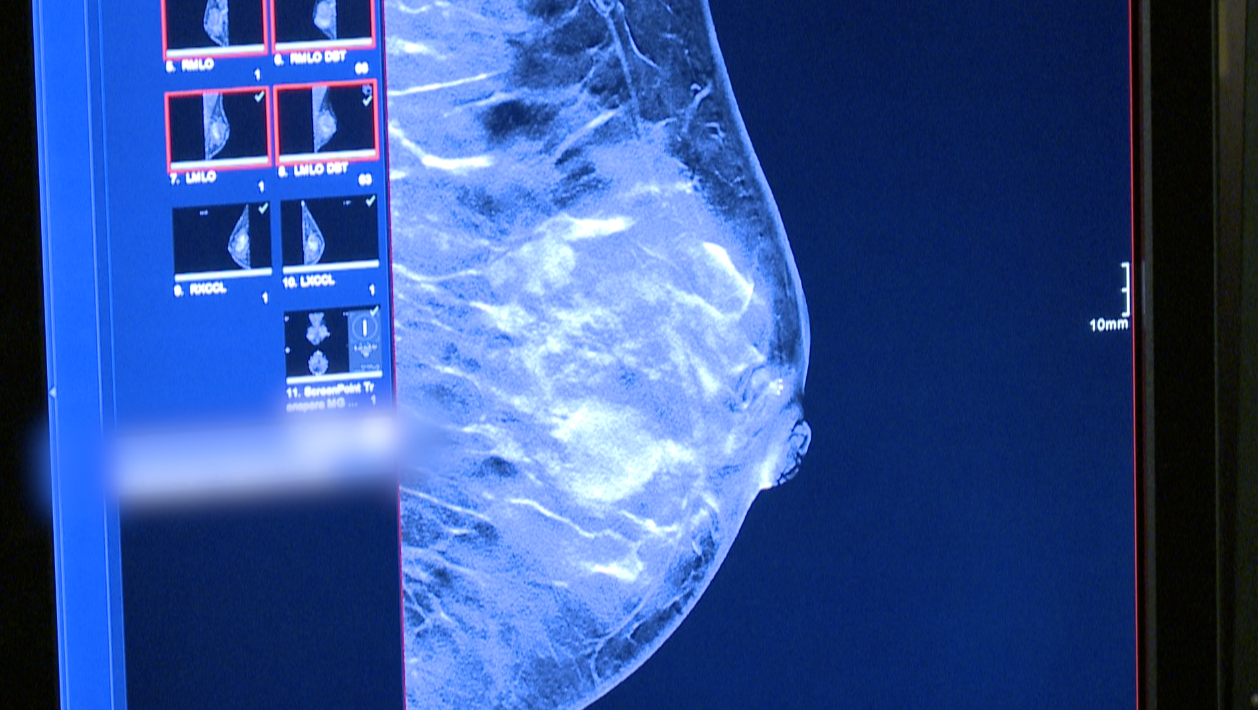

After receiving a 3D mammogram – which studies reveal have improved screening outcomes –Dr. Pettus reviewed Bocks’ scans with the help of the Transpara Breast Care artificial intelligence portal. The use of the technology comes at no extra cost to any patient at Riverside, he said.

The artificial intelligence flagged an area of Bocks’ scan as an “Intermediate Risk”.

“It’s giving this particular lesion an intermediate score,” said Dr. Pettus. “It’s not an overly suspicious kind of look to the AI, but it’s concerned about something.”

Dr. Pettus said, after reviewing Bocks’ previous mammogram to compare how the area of concern has changed, “[the AI’s scoring is] helpful information to me because this patient has multiple cysts everywhere, but unlike [her] other cysts that have a really defined edge to me, the one it’s scoring does have a subtlety questionable edge.”

Based on his own experience reading mammograms, the artificial intelligence’s scoring, and Bocks’ family history, Dr. Pettus ordered an ultrasound of the area of concern.